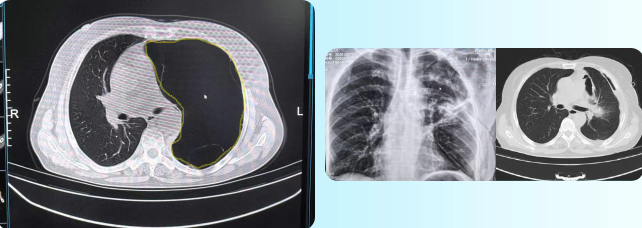

该患者64岁,女性,主因左侧背部疼痛来诊。影像学检查发现,其胸腔内存在一个体积达20×30厘米的巨大肺囊肿,严重压迫心脏及正常肺组织,不仅影响日常生活,还存在猝死的风险。

面对这一复杂病例,胸心外科王圆主任带领团队细致研读影像资料,深入分析病情,并组织多学科讨论,最终制定了胸腔镜微创手术治疗方案。在完善相关检查后,患者如期接受手术。手术团队借助胸腔镜,在狭小的胸腔空间内小心翼翼分离严重粘连的组织。但是,术中发现的实际情况比预想的更为复杂。由于囊肿大,正常解剖结构已完全被破坏,滋养血管密布如“蜘蛛网”,稍有不慎就可能引发大出血。

在麻醉医生和手术护士的紧密配合下,主刀医生精准操作,最终历时5小时,完整切除囊肿壁。术后,受压肺组织顺利复张,纵隔偏移得以纠正,心肺结构基本恢复至正常生理形态,患者胸痛、憋气等症状完全消失。